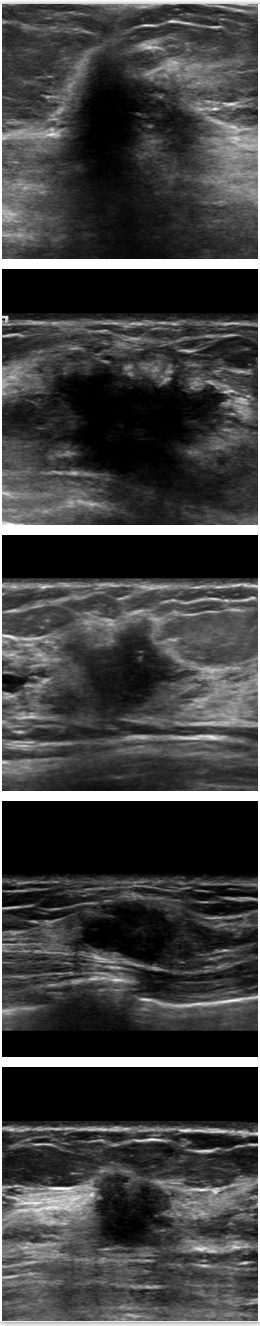

Refer to caption

Figure 6: Comparison of SPCGAN and other segmentation methods of benign lesions. (a) shows original image of benign lesions, (b) shows the manual annotation, (c) shows the result of SPCGAN ,(d), (e) and (f) show results from ResNet, Mask R-CNN and level set.

Fig.6 displays the segmentation results of our SPCGAN, FCN(ResNet), Mask R-CNN and the level set method from benign lesions. Compared with the FCN(ResNet) (d), Mask R-CNN (e) and the level set (f) method, the results of our SPCGAN (c) show good agreements with the manual contours of the lesions. The segmentations from SPCGAN are very close to manual segmentations.